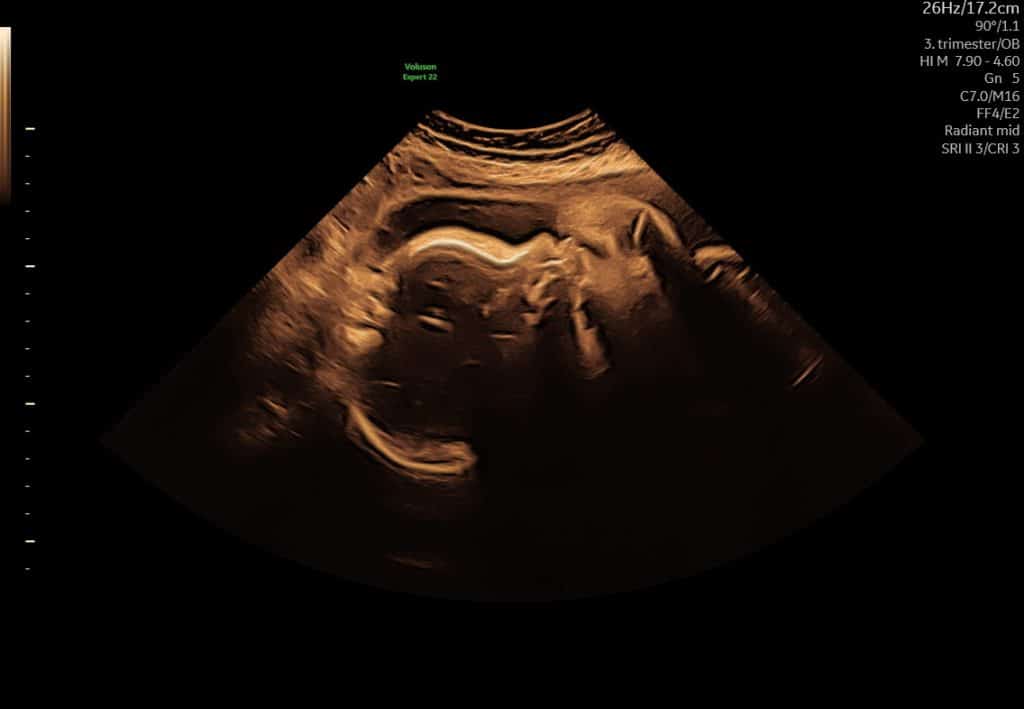

Ultralyd i sen graviditet (uge 29–36)

I tredje trimester fokuserer ultralyd ofte på:

- barnets vækst og trivsel

- fostervandsmængde

- barnets placering i livmoderen

Barnet fylder nu meget, og man kan sjældent se hele barnet på ét billede. Det er helt normalt og betyder ikke, at billedkvaliteten er dårlig.

Ultralyd i sen graviditet. Det er normalt, at man kun ser dele af barnet ad gangen.

3D-ultralyd omkring uge 30 giver ofte et første indtryk af barnets ansigtstræk. Kinder, næse og mund kan være synlige, men billedets udtryk afhænger i høj grad af barnets stilling og pladsforholdene i livmoderen.